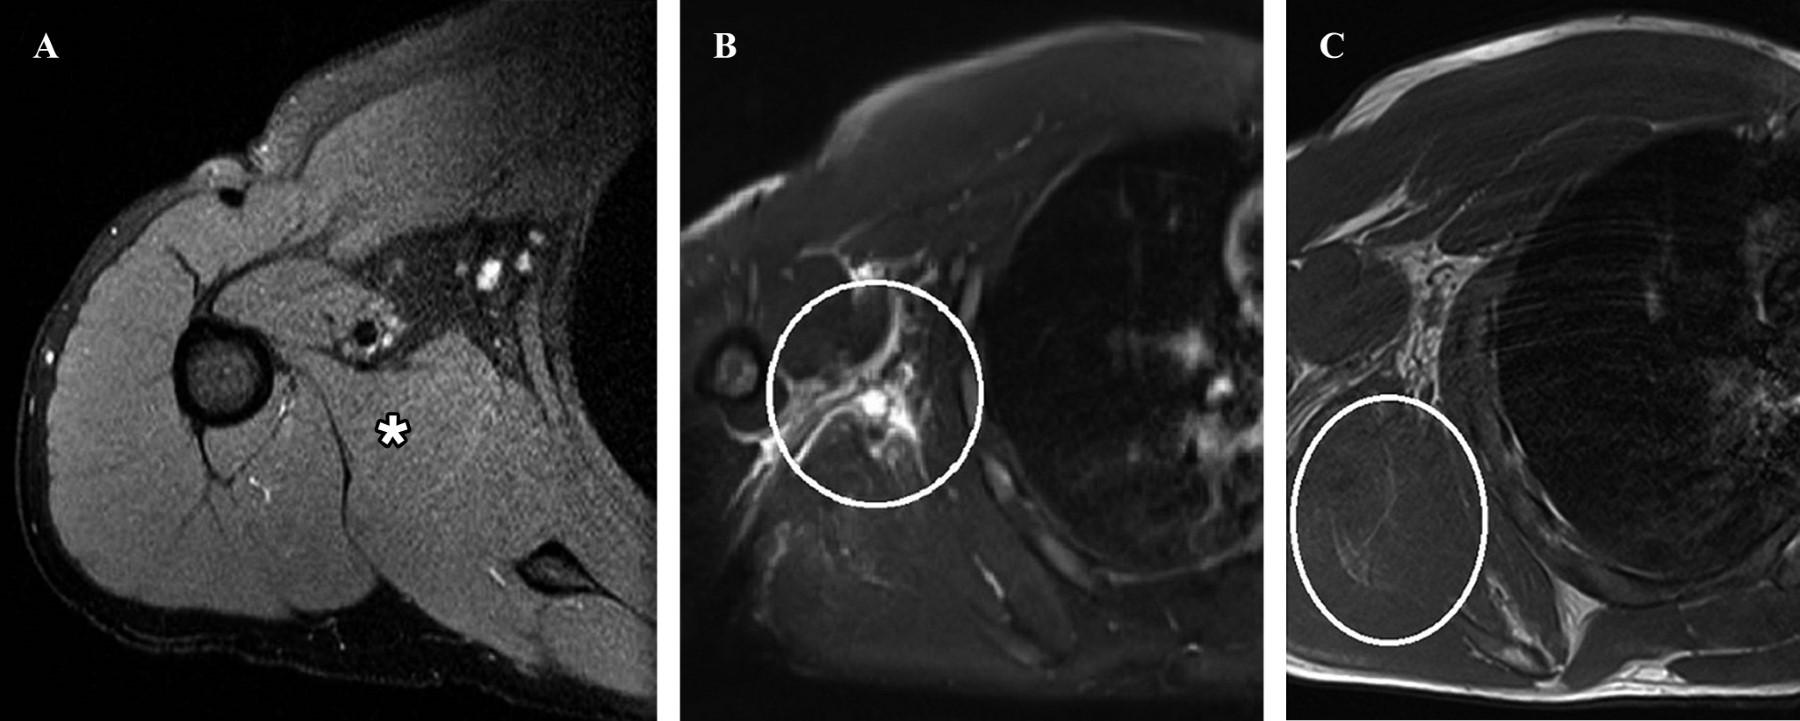

La rotura del músculo redondo mayor es una afección muy conocida en actividades deportivas como el béisbol, el hockey y el tenis. No existe un consenso real en la literatura sobre el tratamiento, y los enfoques varían entre métodos funcionales y quirúrgicos. Si bien el tratamiento funcional parece ser una opción viable, falta evidencia que indique una mejora significativa en la fuerza de rotación medial después de dicho tratamiento. Presentamos a un hombre de 30 años con dolor debajo de la axila derecha durante los últimos 10 días, atribuido al entrenamiento de jiu-jitsu, que reveló un desgarro completo de la unión musculotendinosa del redondo mayor y un desgarro de inserción parcial (aproximadamente el 75% de espesor) de los tendones supraespinoso e infraespinoso, junto con atrofia en la transición musculotendinosa del pectoral mayor. El paciente fue tratado con medicación analgésica, acompañada de tratamiento fisioterapéutico que incluyó electrotermofototerapia, terapia con láser/LED, terapia manual y un régimen de ejercicio estructurado durante 14 semanas, reintroduciendo gradualmente el entrenamiento deportivo específico.

Figura 2